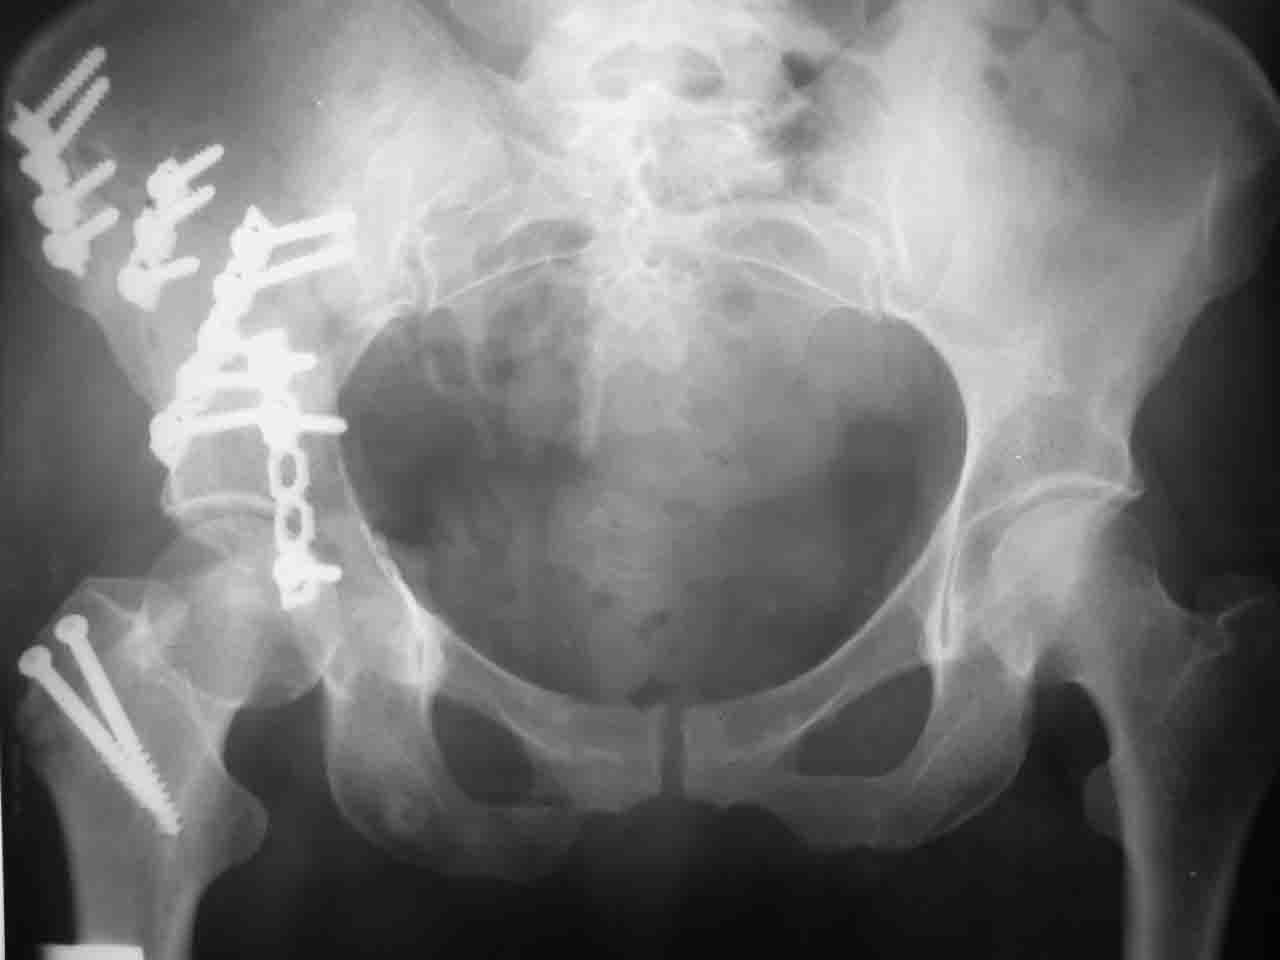

Снимки и схема